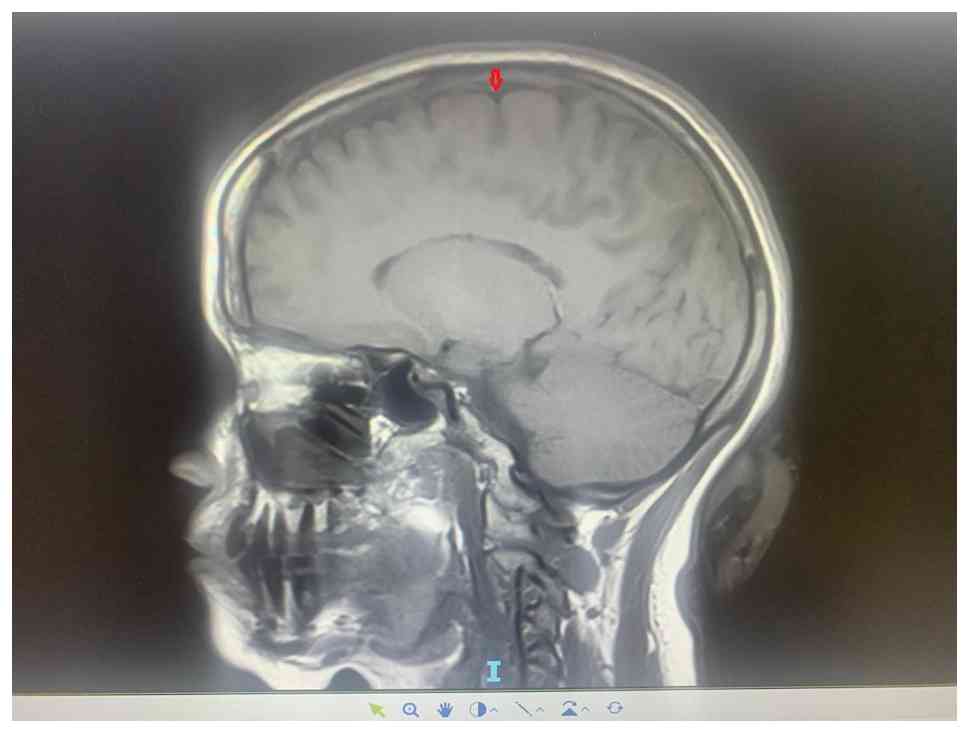

At the time of diagnosis, the patient had no blurring of vision or epigastric pain. Vital signs and blood pressure were normal; there was no proteinuria, thus excluding the possibility of pregnancy-induced hypertension. Meningitis and hyperemesis were also unlikely because of the absence of fever, meningeal signs, severe vomiting and dehydration. There was no neurological deficits detected therefore the possibility of a stroke was remote; thus, the severe persistent headache prompted ophthalmologic examination by fundoscopy, which suggested papilledema (bilateral grade 4). MRI (Fig. 1, Fig. 2 and Fig. 3) and MR venography (MRV; data not shown) showed thrombosis involving the superior sagittal sinus without ischemia or hemorrhage. The patient was prescribed enoxaparin (LMWH) 100 mg twice daily (subcutaneous administration) for thrombosis and acetazolamide 500 mg twice a day (subcutaneous administration) for the papilledema attributed to the dural sinus thrombosis.

MRI T1-weighted mid sagittal section.

The arrow shows high intensity in the superior sagittal sinus.

Image was obtained in June 2023.

Figure 1

MRI T1-weighted mid sagittal section. The arrow shows high intensity in the superior sagittal sinus. Image was obtained in June 2023.